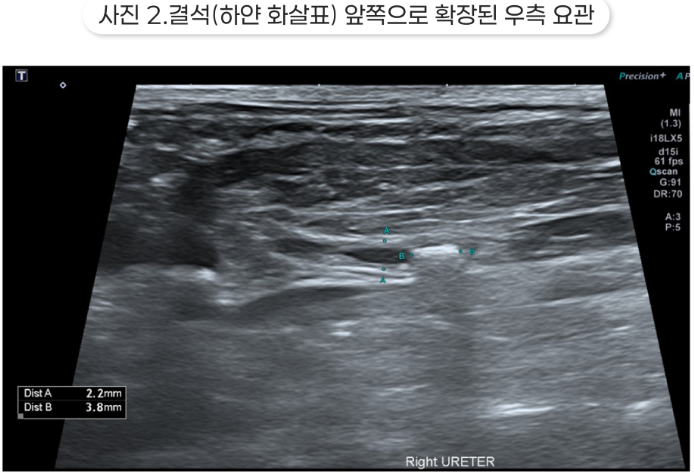

방사선 영상에서는 복수로 인해 복강 장기 전체가 보이진 않았지만 양측 신장이 모두 크게 나타났고, 특히 좌측 신장이 더 크게 나타났습니다.

초음파 영상에서는 양측 수신증과 요관 결석이 확인되었습니다.

결석보다 가까운 쪽의 요관은 확장되어 있는데, 이는 요관 폐색을 의미합니다. 신우가 매우 확장되어 있었고, 특히 오른쪽 신장은 피질이 많이 얇아져 있고 심한 수신증 소견을 보였습니다.